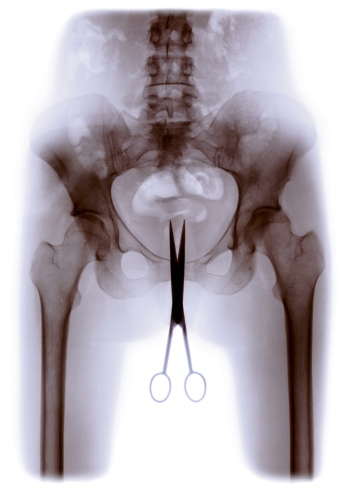

X-RAY showcases a broad spectrum of X-ray technology and its many applications, including early laboratory apparatus and X-ray images, the Pedoscope shoe-fitting machine (introduced around 1920), and X-ray satellites such as eROSITA, which are used to explore galaxies and investigate dark matter in space. The central theme of the exhibition is the transillumination – whether close-up or from afar – of animate and inanimate matter. Exhibits include the “Transparent Human”, which was created at the end of the 1920s by the Deutsches Hygiene-Museum in Dresden. This iconic representation of X-ray vision provides a view of the complex structures within the human body.

Meanwhile, imaging techniques based on X-rays have steadily progressed, leading to the development of, for example, computer tomography (CT). In parallel, the ability to limit exposure to radiation during examination has improved immeasurably. And yet, whereas radiology is now routine in the medical sphere, artists around the world have retained their fascination with this phenomenon and have produced a host of works that use X-rays, incorporate X-ray images or harness the idea of X-ray vision.

The creative means employed in such works include original X-ray images, which are cropped, painted over, or modified, augmented and collaged with different materials and colours; digitally enlarged images that serve as templates for glass windows; and graphic simulations of the X-ray process. Similarly, radiological motifs are incorporated in paintings, sculptures and graphics. And skull X-rays feature as a motif in the vanitas genre along with skeletons and individual bones, both continuing in idiosyncratic fashion a long tradition of memento mori and danse macabre.